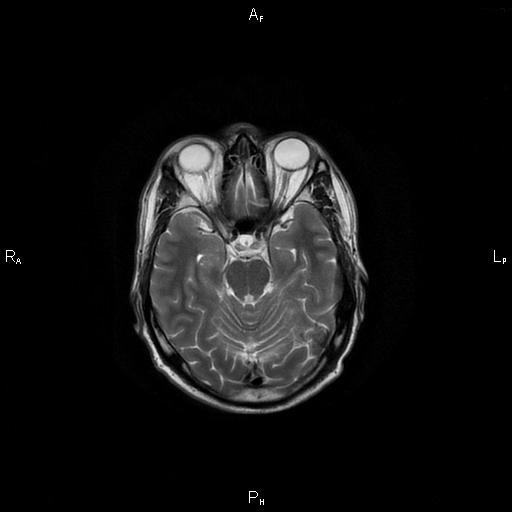

4. Рис. 1а

Тема

Тип Материалы исследования

Посмотреть (29KB)

Метаданные ▾

5. Рис. 1б

Посмотреть (28KB)